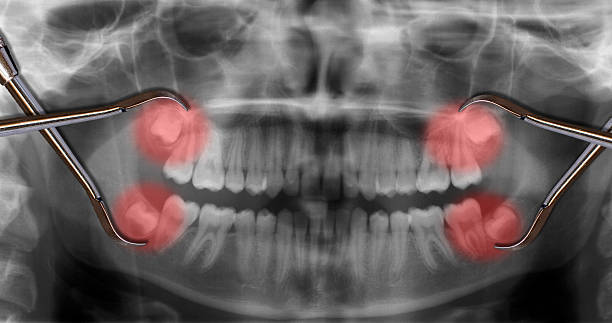

사랑니 발치를 앞두고 있거나 이미 발치한 분들이 가장 궁금해하는 것 중 하나가 바로 '뭘 먹어야 할까?' 그리고 '통증을 어떻게 줄일 수 있을까?' 하는 점일 텐데요.

오늘은 사랑니 발치 후 추천 식사 메뉴와 통증 줄이는 방법에 대해 자세히 알려드리겠습니다!